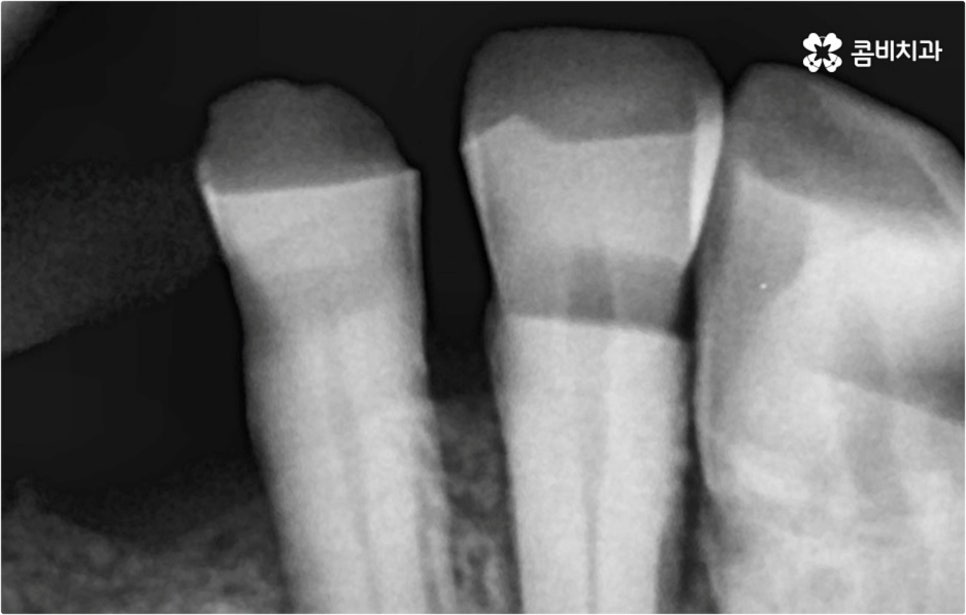

이때 환자분들의 상황에 따라서 임플란트 시술이 어려운 분들도 있을 수 있고 시술 전에 다른 치료를 선행해야 하는 분들도 있을 수 있기 때문에 먼저 꼼꼼하게 검진을 받아보실 필요가 있습니다. 특히 대다수의 치아를 잃어버리고 전악임플란트 를 진행하시는 분들의 경우 원인에 따라서 대처 방법이 다를 수 있는데요.

예를 들어 사고를 통해 한꺼번에 여러 개의 치아가 부러지거나 빠진 경우 연령 또는 전신 질환 여부 등을 살펴보고 치조골 상태가 양호하다면 보다 빠르고 간편한 당일 식립 방식을 이용해 볼 수 있어요. 그러나 하나 둘씩 치아가 빠질 때 마다 제때 치료를 해 주지 않아 치료 시기를 놓치고 결과적으로 무치악 상태에 이른지 오래 된 경우 또는 틀니를 오래 착용하여 잇몸뼈가 이미 많이 내려앉은 경우라면 바탕이 되는 잇몸뼈를 보충해 준 후 식립을 진행하는 방식을 이용해야 할 거예요.

또한 상악동과의 거리가 짧다면 거상술을 선행해야 할 수도 있고 심각한 치주 질환이 원인이라면 이를 먼저 깨끗하게 치료해 준 후 식립을 진행해야 성공률 또는 지속률이 높아질 수 있어요.